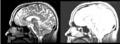

Original file(1,162 × 426 pixels, file size: 306 KB, MIME type: image/png)

Registration of a t2w image to arbitrary t1 and back via the BSpline selection in the Register Images module.